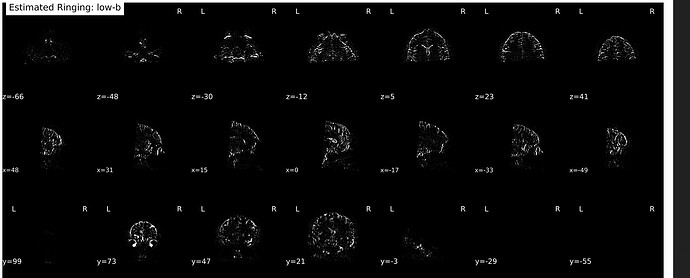

So I thought maybe it might have something to do with running dwidenoise first—went and tested out RPG on a couple raw scans (no reorenting to LPS or MP-PCA, just run locally on my machine via the TORTOISE Docker container), and much to my surprise…

It switched! Now the cutoff is a bit more rostral along the PE axis and it’s just the posterior portion of the brain that seems to have estimated/removed Gibbs artifacts. Here’s an example from a cs-DSI collected in May of this year (absolute value overlaid after subtracting the first raw and unrung b=0 volume):

And one using the Q4 sampling scheme (same site but prior to a gradient coil replacement):